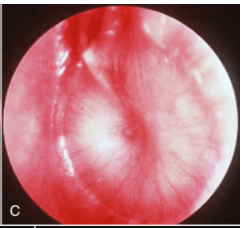

Describe the physical exam finding shown in the picture below.

What is an erythematous, bulging (loss of landmarks) TM?